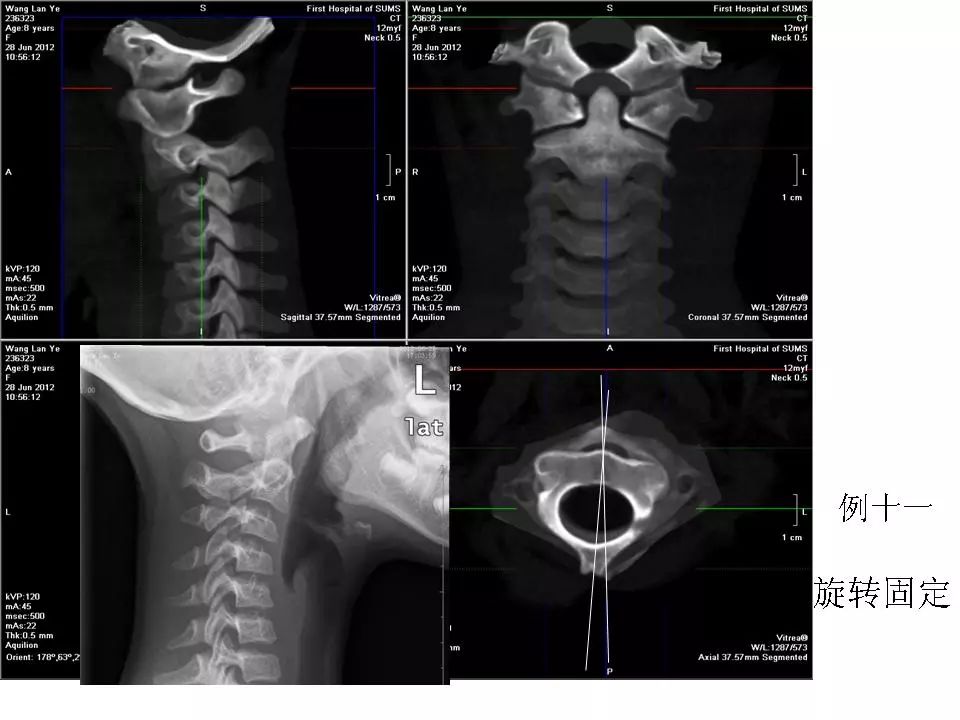

寰枢关节脱位的影像诊断